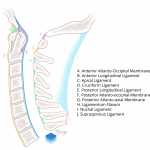

Acute fracture-subluxation at the craniocervical junction with multiple tiny acute displaced fractures along the anterior aspects of both C1 superior articular facets, mild anterior subluxation of the occipital condyles relative to C1, widening of the posterior aspect of both atlanto-occipital joints, widening of the C1-C2 interspinous interval, and widening of the superior aspect of the sagittal atlantodental interval. MRI could further evaluate the extent of ligamentous injury.